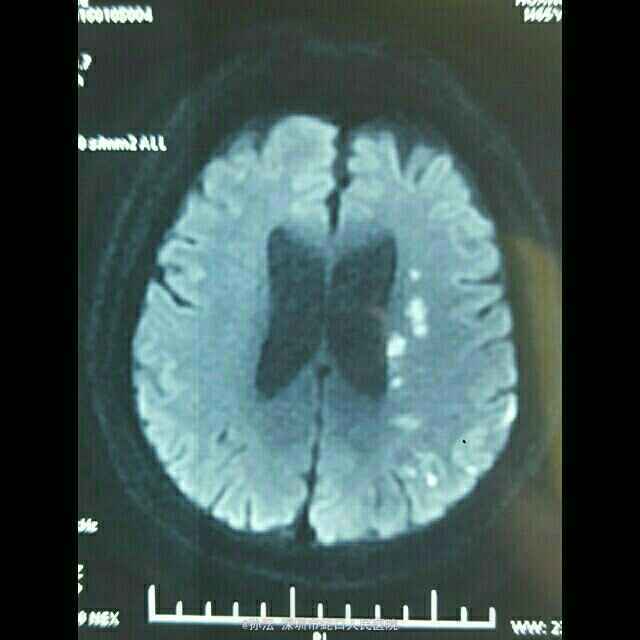

65岁男性,突发言语不利伴四肢乏力2天。 2天前无明显诱因突然言语不利,吐字不清,伴四肢乏力,以双下肢明显,表现为行走笨拙,伴肢体麻木,无头晕、头痛,无饮水呛咳、流涎,无意识不清、大小便失禁,无四肢抽搐。既往血压偏高5年,未使用降压药,血压未监测。

查体:BP 149/85mmHg,心肺听诊无异常。腹平软,无压痛、反跳痛,双下肢无水肿。神经系统检查:神志清楚,构音不清,记忆力、定向力、理解力、计算力均下降,两眼球活动自如,未见震颤,双瞳等大等圆,光反射灵敏,两侧额纹对称,右侧鼻唇沟浅,伸舌偏右,咽反射灵敏,颈软,四肢肌力5级,肌张力正常,腱反射对称,右侧病理征可疑阳性,共济征阴性,克氏征、布氏症阴性。NIHSS评分4分。 门诊头颅CT提示:脑萎缩。血液流变检测:全血粘度低切9.76mPa.s。糖化血红蛋白测定 HbA1c 6.60%。头颅MRI平扫(3.0T)示:左侧大脑分水岭区急性脑梗塞。脑小血管病变,FazekasⅡ级;轻度老年脑改变、部分空泡蝶鞍。

定位于左侧大脑中动脉及后动脉,定性动脉粥样硬化性血栓形成。 治疗上予依达拉奉清除自由基、奥拉西坦脑保护、血栓通改善微循环、阿司匹林抗血小板聚集、阿托伐他汀抗动脉硬化及对症治疗。